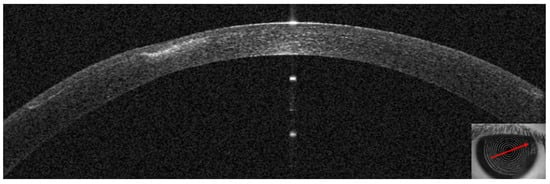

3.3. Patient #3